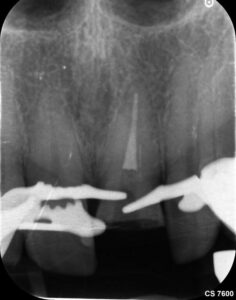

In diesem Fall geht es um einen männlichen Patienten, 54, Diabetes mellitus, leichter Raucher. Er ist seit 2016 Stammpatient im Haus. Der Patient wurde intern zur Wurzelkanalbehandlung überwiesen. Der Schneidezahn 21 wies nach einem Trauma eine unkomplizierte Kronenfraktur in Höhe der Schmelz-Zement-Grenze auf. Der Patient wurde bei AllDent Frankfurt am Karfreitag 2025 im Notdienst erstversorgt. Das Bruchstück konnte sowohl im Notdienst als auch bei der Kontrolluntersuchung bei seinem Stammbehandler, Ans Tawel (M.Sc) am 9. Mai wieder befestigt werden.

Vier Wochen nach der Erstversorgung erschien der Patient zur Wurzelkanalbehandlung. Der Schneidezahn 21 war zu dem Zeitpunkt noch vital. Der Patient klagte allerdings über immer häufiger werdende Schmerzintervalle sowie zunehmende Reaktionen auf Wärme. Das Parodontium zeigte sich ohne pathologischen Befund mit Sondierungstiefen bis drei Millimeter. Über die Fraktur hinausgehende Verletzungen wurden im Notdienst nicht dokumentiert und konnten zum Behandlungstermin ebenfalls nicht diagnostiziert werden.

Das Zahnfragment hatte eine gute Passung auf den frakturierten Stumpf. So konnte im Vorfeld ein Silikonabdruck als Vorwall für den Kompositaufbau erstellt werden. Die endodontische Therapie sowie der Füllungsaufbau erfolgten ausschließlich unter dem hochauflösenden OP-Mikroskop (Zumax OMS2350). Die zu behandelnde Region wurde mit Ubistesin 1/200000 lokal betäubt. Anschließend wurde von 11 bis 22 ein Kofferdam angebracht. Der Zahn wurde mit einem konischen Diamanten trepaniert, die Trepanationsöffnung mit Gates-Glidden-Bohrern erweitert. Die Aufbereitung erfolgte mit dem Reciproc Blue System bis zur Größe 50.05.

Es wurde mit 15 Milliliter Natriumhypochlorid und 2,5 Milliliter EDTA gespült. Beide Flüssigkeiten wurden mittels PUI (assive Ultrasonic Irrigation) aktiviert.

Die Wurzelfüllung erfolgte in Continuus Wave Technik und Backfill in zwei Inkrementen mit

Guttapercha und AH Plus als Sealer. Anschließend wurden aufgrund der ovalen Kavität zwei Glasfaserstifte zur Stabilisation der Füllung eingebracht und mit Luxacore adhäsiv verklebt.